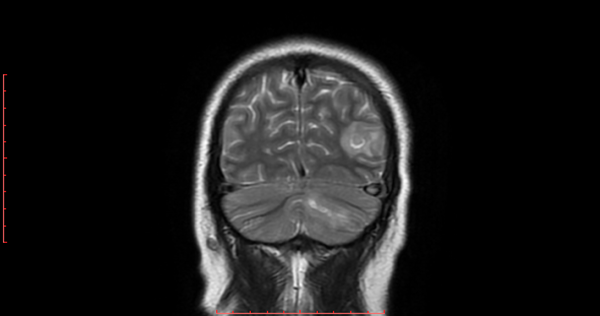

h. 3) Resonancia magnética cerebral corte coronal en secuencia T2. Se encontró zona focal heterogénea de predominio hiperintensa sin efecto de masa en lóbulo parietal izquierdo. En el hemisferio cerebeloso se observó imagen de forma lineal hiperintensa con edema perilesional. (Figura 3).

Figura 3. Resonancia magnética cerebral corte coronal en secuencia T2.